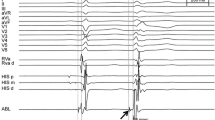

In six healthy canines, VF mapping was performed continuously using multielectrode mapping basket catheters placed in the RVOT and distal RV and LV. The mean duration from induction of VF to asystole was 54 ± 9 min (range 42–70 min). In all six canines, VF terminated in the LV prior to the RV. Despite local termination of VF with the LV being in a ventricular escape rhythm, VF persisted in the RV and on the surface ECG (Fig. 2, middle panel). The mean duration of VF activity in the LV was 49 ± 6 min, whereas the mean duration of VF activity in the RV was 54 ± 9 min (Table 1). With spontaneous termination of VF activity in the RV to a ventricular escape rhythm, there was a cessation of VF with an escape rhythm noted on the surface ECG (Fig. 2, bottom panel). Post-VF termination, ventricular capture with pacing in both the RV and LV was demonstrated. However, despite aggressive ventricular burst pacing at cycle lengths from 400 ms down to 200 ms in both the RV and LV, we were unable to reinduce sustained VF (Fig. 3).

3.1.1 Early VF

The regional differences of ventricular CL during VF are summarized in Table 2 and Fig. 4 A. Immediately after induction of VF, the shortest ventricular CL occurred in the distal LV (92 ± 6 ms). The ventricular CLs were not significantly different in the RVOT, nor the other RV and LV regions, when compared to the distal LV (Table 2). After 5 min of VF, the shortest ventricular CL occurred in the RV free wall (79 ± 7 ms), and the CL of VF was significantly slower in the distal LV (91 ± 5 ms, p = 0.016), the LV septum (90 ± 6 ms, p = 0.016), the LV inferior wall (110 ± 24 ms, p = 0.016), and the RVOT (101 ± 14 ms, p = 0.012), comparatively. After 10 min of VF, the shortest ventricular CL occurred in the RV free wall (72 ± 6 ms), and the CL of VF was significantly slower in the distal LV (83 ± 5 ms, p = 0.016), the LV septum (87 ± 7 ms, p = 0.008), the LV anterior wall (84 ± 3 ms, p = 0.012), and the RVOT (110 ± 25 ms, p = 0.008).

3.1.2 Late VF

Across the rest of VF, the shortest ventricular CL was in the RV septum (82 ± 15 ms) after 20 min, the distal RV (99 ± 22 ms) after 30 min, the RV free wall (130 ± 21 ms) after 40 min, and the distal RV (111 ± 2 ms) after 50 min of VF. There was no significant difference in the ventricular CLs in the RVOT and the different LV and RV regions as compared to the regions with the shortest CLs at each time interval during this period (20 to 50 min of VF).

There was a trend towards an increase in the ventricular CLs over time (Table 2 and Fig. 4 A) from an average of 95 ± 8 ms in all 5 canines immediately after VF induction to an average of 154 ± 33 ms after 40 min of VF (p = 0.063). Mapping data for individual animal experiments are available in Supplemental Tables.